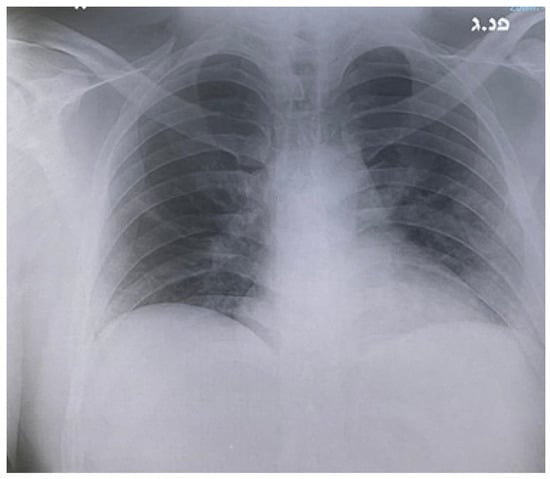

Rapid Clinical and Radiological Improvement in a Patient with Severe COVID-19 Infection Treated with Convalescent Plasma

2. Case Report